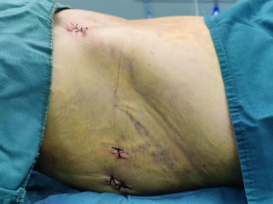

术后下腹部前面外观:

术后臀部左、右外观: